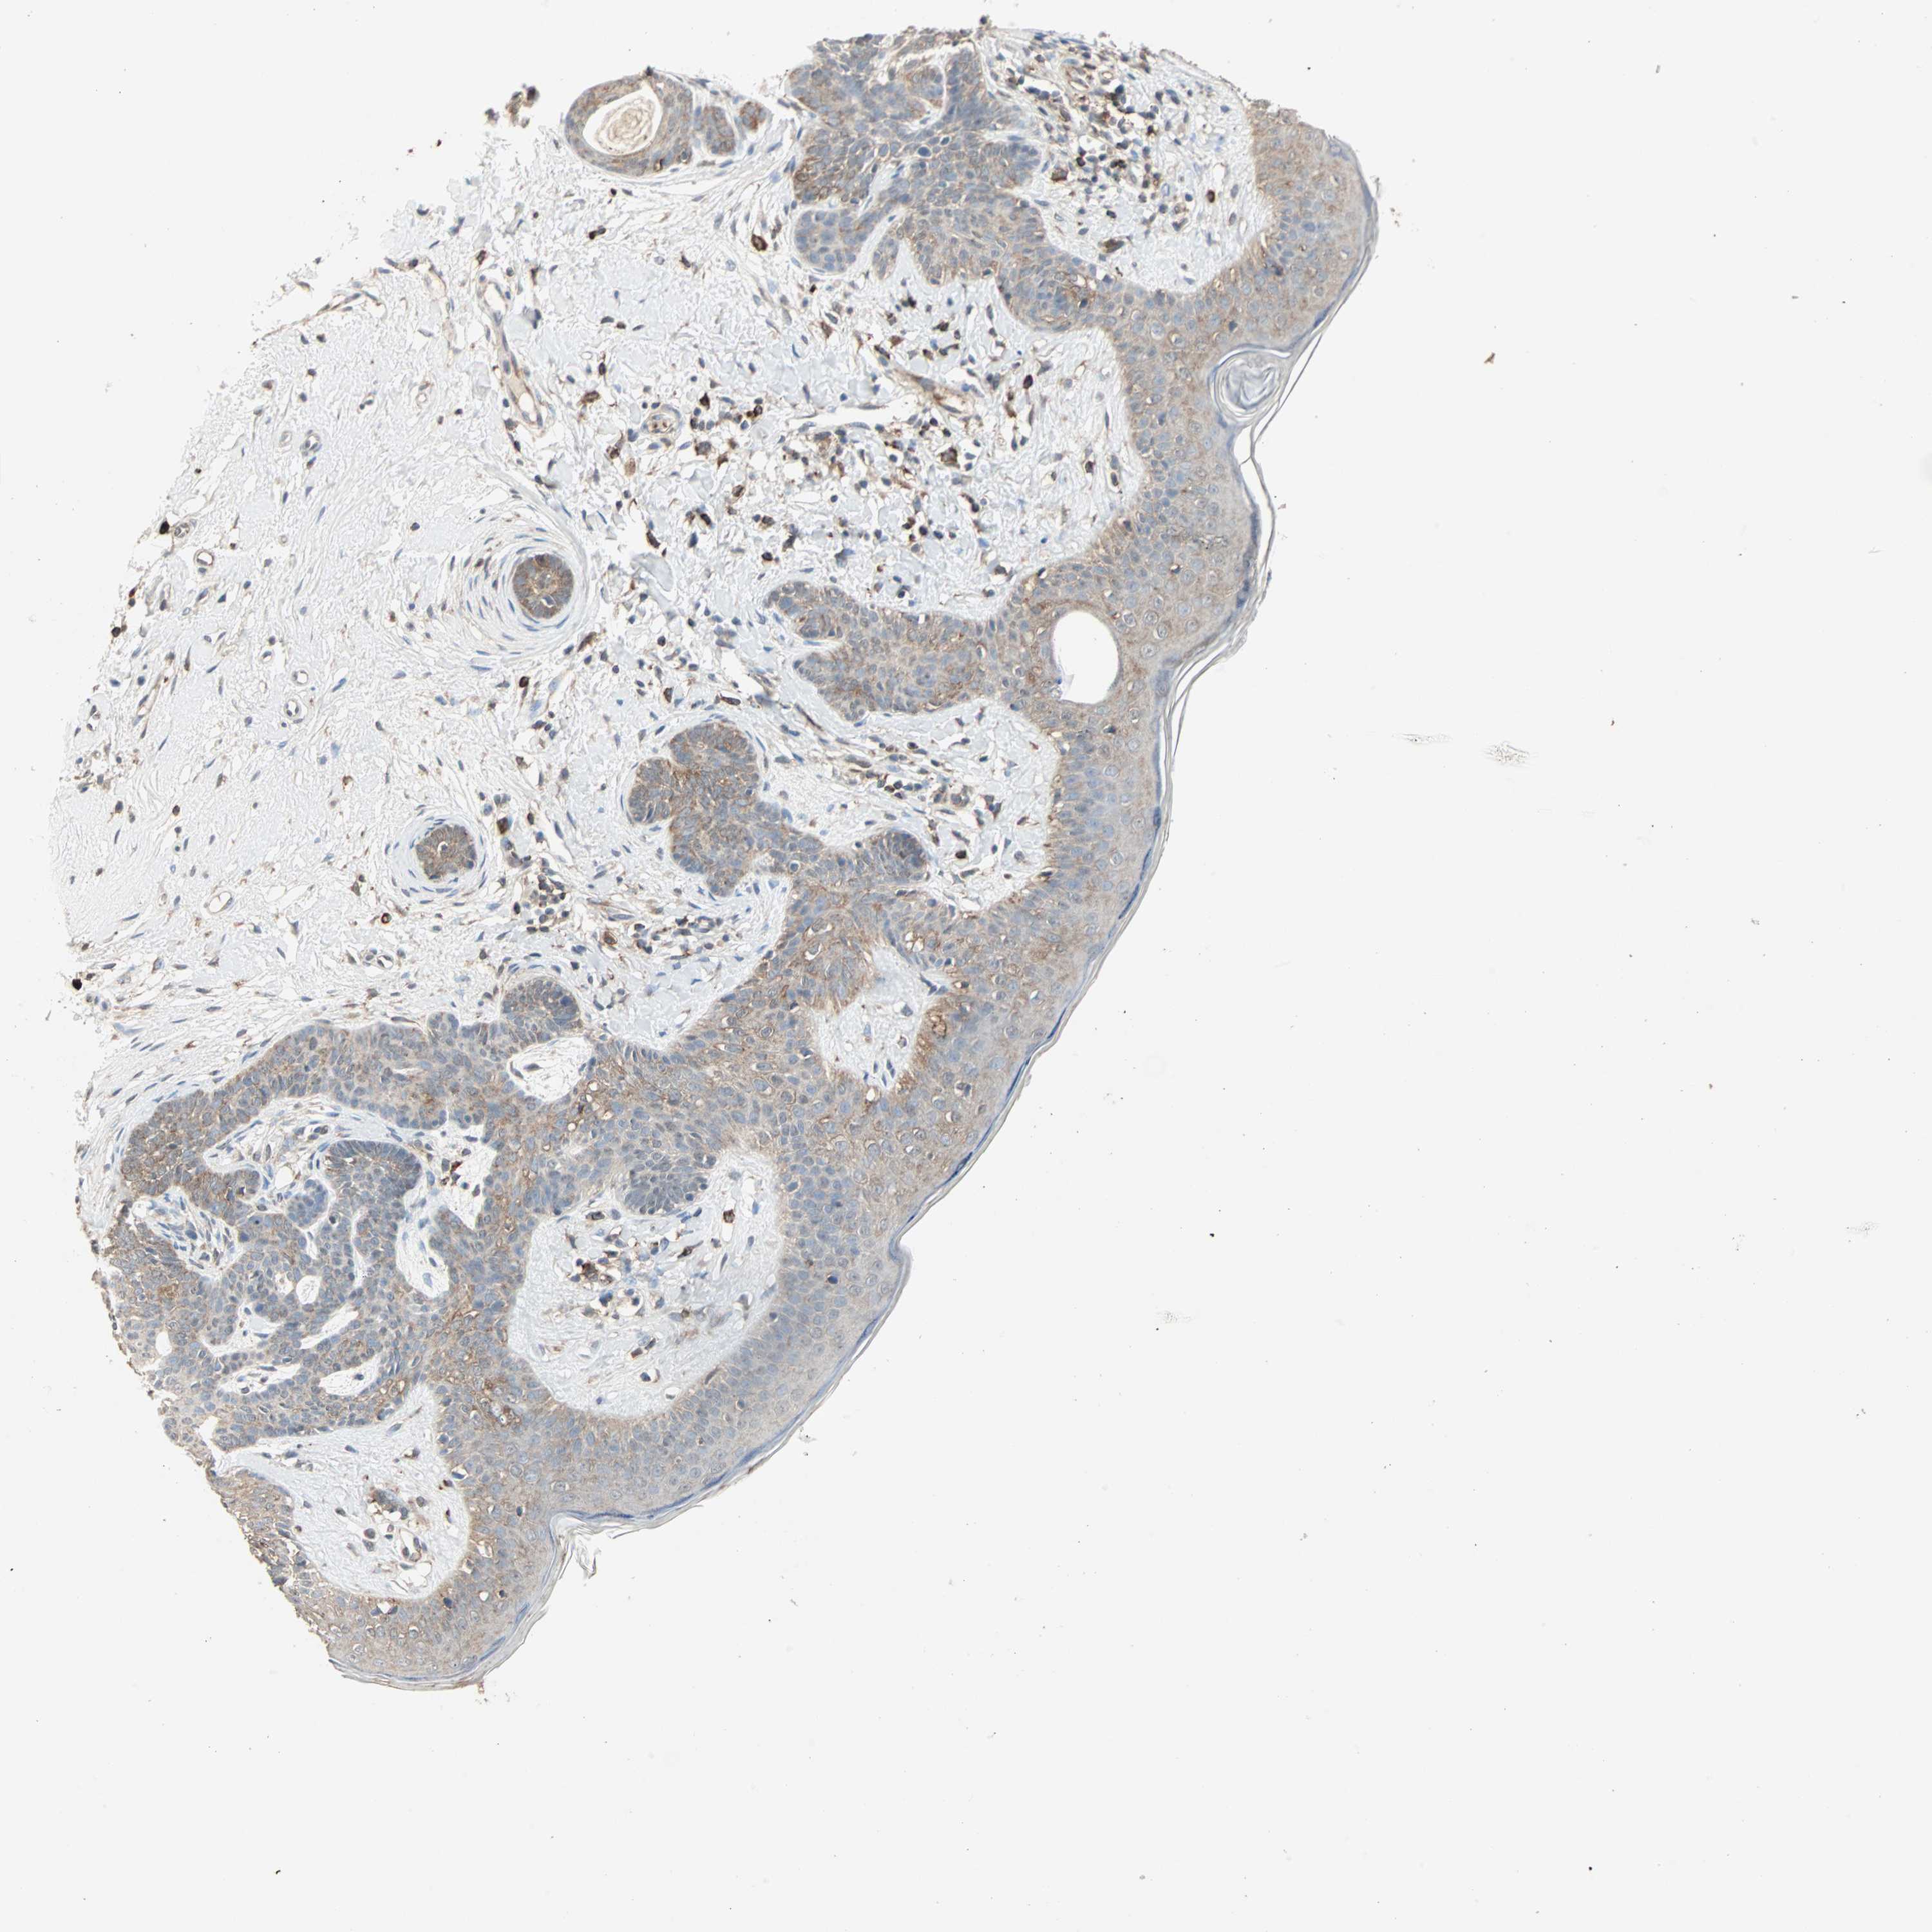

SKIN CANCER - Protein expressioni

A mouse-over function shows sample information and annotation data. Click on an image to view it in a full screen mode. Samples can be filtered based on level of antibody staining by selecting one or several of the following categories: high, medium, low and not detected. The assay and annotation is described here.

Antibody stainingi

Antibody staining in the annotated cell types in the current human tissue is reported as not detected, low, medium, or high, based on conventional immunohistochemistry profiling in selected tissues. This score is based on the combination of the staining intensity and fraction of stained cells.

Each image is clickable and will lead to virtual microscopy that enables deeper exploration of all samples and also displays staining intensity scores, fraction scores and subcellular localization as well as patient and tissue information for each sample.

Antibody HPA007875

Staining

High

Medium

Low

Not detected

Intensity

Strong

Moderate

Weak

Negative

Quantity

>75%

75%-25%

<25%

None

Location

Nuclear

Cytoplasmic/membranous

Cytoplasmic/membranous,nuclear

Squamous cell carcinoma, NOS